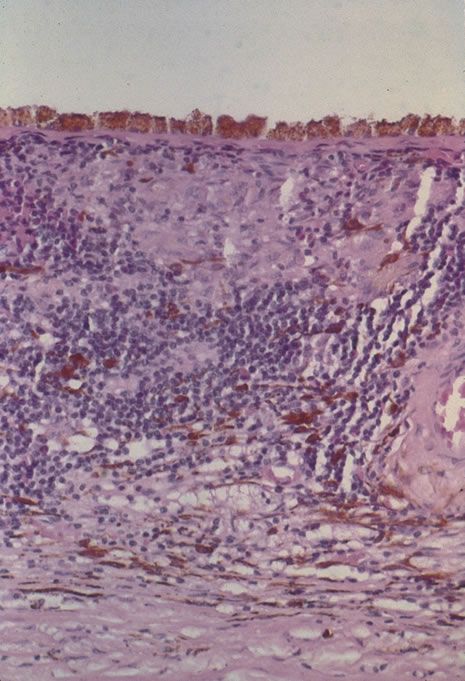

Classic histopathology consists of caseating granulomatous inflammation in a zonal distribution. The noncaseating tubercle may be present but is less specific (Fig. 18). The organism is acid-fast, meaning that it does not decolorize with acid alcohol after staining with basic fuchsin, appearing as bright red, long thin rods. A definitive laboratory diagnosis of intraocular tuberculosis may be made via anterior chamber tap, vitreous or chorioretinal biopsy depending on the site of inflammation. The PCR may be helpful in making the diagnosis.

Fig. 18. Histopathologic examination of an enucleated eye demonstrates a caseating focus in the choroid.